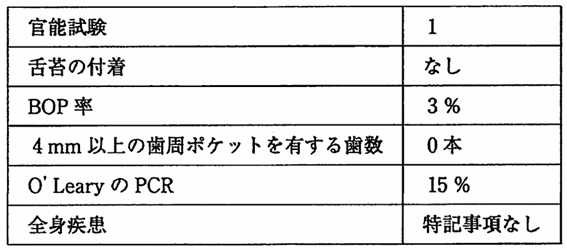

午前-77

レジン系小窩裂溝填塞材を用いて模型上で予防填塞を行っている過程の一部の写真を別に示す。 この処置の目的はどれか。2つ選べ。

a.歯面の清掃

b.感染歯質の除去

c.歯質の再石灰化

d.接着効果の向上

解答を見る

a.d